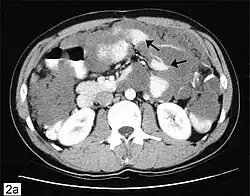

A very large ovarian cancer as seen on CT

CT scanning is preferred to assess the extent of the tumor in the abdominopelvic cavity, though magnetic resonance imaging can also be used.[28] CT scanning can also be useful for finding omental caking or differentiating fluid from solid tumor in the abdomen, especially in low malignant potential tumors. However, it may not detect smaller tumors. Sometimes, a chest x-ray is used to detect metastases in the chest or pleural effusion. Another test for metastatic disease, though it is infrequently used, is a barium enema, which can show if the rectosigmoid colon is involved in the disease. Positron emission tomography, bone scans, and paracentesis are of limited use; in fact, paracentesis can cause metastases to form at the needle insertion site and may not provide useful results.[29] However, paracentesis can be used in cases where there is no pelvic mass and ascites is still present.[29] A physician suspecting ovarian cancer may also perform mammography or an endometrial biopsy (in the case of abnormal bleeding) to assess the possibility of breast malignancies and endometrial malignancy, respectively. Vaginal ultrasonography is often the first-line imaging study performed when an adnexal mass is found. Several characteristics of an adnexal mass indicate ovarian malignancy; they usually are solid, irregular, multilocular, and/or large; and they typically have papillary features, central vessels, and/or irregular internal septations.[31] However, SCST has no definitive characteristics on radiographic study.[32]